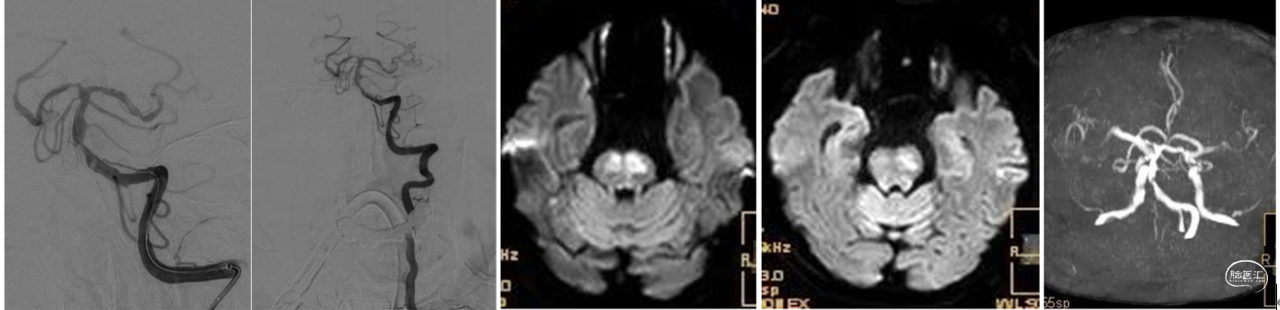

造影显示左侧椎动脉为优势血管,基底动脉闭塞部位呈笔尖征,结合临床症状提示ICAS病变(下图1、2)。首过效应阳性(下图3),释放4×30mm Syphonet®取栓支架,可见支架通体显影(下图4),支架中部呈现蜂腰征,辅助判断病变部位。

Syphonet®取栓支架释放后造影,可见前向血流部分恢复(下图1)。沿Syphonet®取栓支架的输送导丝推送2.5×15mm Maverick球囊至狭窄段,将取栓支架部分回收至球囊导丝腔(下图2)。

充盈球囊处理近端狭窄(下图1)。球囊泄压后前进中间导管越过病变(下图2)。

中间导管联合Syphonet®取栓支架进行远端取栓(下图1)。取出的血栓(下图2)。取栓后再次释放Syphonet®取栓支架,可见支架打开良好,蜂腰消失(下图3、4)。

造影判断血管再通良好,回收Syphonet®取栓支架,将微导丝置于远端等待观察(下图1、2)。术后情况:术后神志转清,左侧肢体肌力5级,右侧4级。